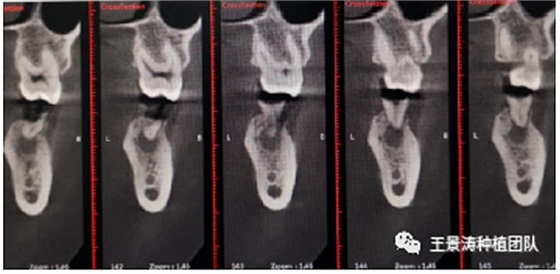

其次初期穩(wěn)定性的獲得,前牙美學(xué)區(qū)種植體的初期穩(wěn)定性主要是依靠腭舌側(cè)骨板及基底骨來獲得的。后牙區(qū)的穩(wěn)定性主要依靠多根牙的牙槽間隔及根尖到重要解剖位置的高度的骨質(zhì)獲得(主要是竇嵴距和管嵴矩的高度,還要參考植入種植體的長度),因此術(shù)前仔細(xì)測量牙槽間隔與根尖至重要解剖結(jié)構(gòu)的高度是后牙即刻種植的關(guān)鍵因素之一。

下述病例則是15區(qū)域的即刻種植,15因牙冠折斷于齦下,無法樁核冠修復(fù),則考慮種植修復(fù)。但拍攝CBCT后發(fā)現(xiàn)根尖距上頜竇底距離較短?;颊邽槟贻p女性,無全身系統(tǒng)疾病且可利用上頜竇底與根尖皮質(zhì)骨雙側(cè)皮質(zhì)骨固位,且此位置可通過頰側(cè)軟組織減張技術(shù)獲得嚴(yán)密封閉牙槽窩。因其根尖距上頜竇距離較低,遂拔除15后行上頜竇內(nèi)提升,埋入式種植,最終修復(fù)的完成。